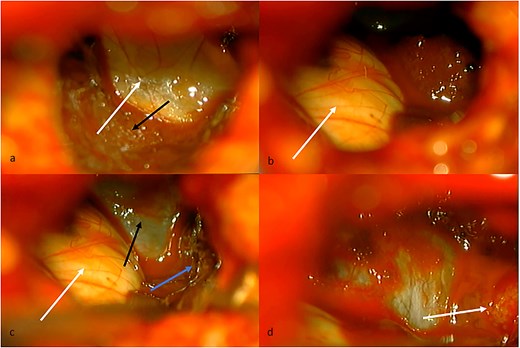

Given the presence of hemorrhage from a probable metastatic lesion on the left parietal, it was decided to undergo craniotomy and tumor resection. It was decided to perform an approach on the previous parietal craniotomy. The patient was placed in the concorde position, and the previous incision was extended. Likewise, the previous craniotomy was extended toward the occipital base. A transulcal posterior parietal approach was performed. The ventricular ependyma was found 5 mm from the parietal cortex, which was opened, and black, chocolate-colored liquid from the left lateral ventricle was found. A dark brown lesion was also observed, adhered to the walls of the lateral ventricle, toward the thalamus, floor of the ventricle, ventricular atrium, and multiple implant areas toward the choroid fissure, choroid plexus, and choroid artery. A subtotal resection was performed since the solid portion of the tumor was found with abundant blood vessels and adhered to the choroid plexus, with abundant bleeding (Fig. 2). The histopathological report confirmed a metastatic lesion in the brain of the thyroid papillary gland. The patient improved neurologically in the immediate postoperative period and was discharged 2 days later with improved consciousness and strength. She continued her oncological treatment, and treatment of the cranial metastatic lesion was complemented with radiotherapy (Fig. 1).

(a) Intraventricular view. White arrow, floor of the left lateral ventricle. Black arrow, tumor tissue covering thalamus. (b) White arrow, thalamus in the anterior, and medial limit of the lateral ventricle. (c) White arrow, thalamus. Black arrow, floor of the lateral ventricle. Blue arrow, tumor tissue covering lateral limit of lateral ventricle. (d) White arrow, choroid fissure with choroid plexus, and choroidal artery.